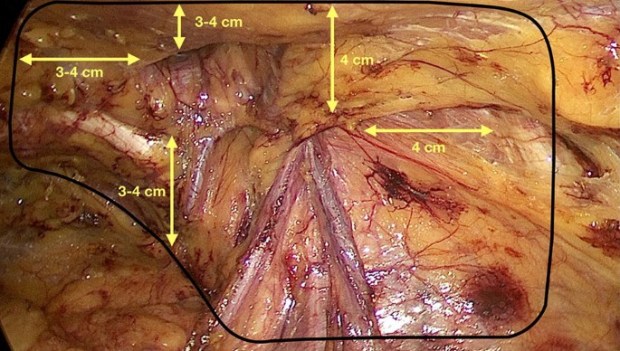

A nivel técnico, la vía laparoscópica permite reparar en un único acto quirúrgico todos los orificios herniados o potencialmente herniables de la región inguinocrural, de forma bilateral sí así se considerara. Ya que la colocación de la malla en el espacio pre-peritoneal consigue cubrir los orificios inguinal indirecto o lateral, inguinal directo o medial, femoral o crural e incluso el obturatriz.

Existen principalmente dos técnicas para la reparación laparoscópica de la hernia inguinal, el abordaje TEP (Total Extra-Peritoneal) y el abordaje TAPP (Trans-Abdominal Pre-Peritoneal) en función de si precisa o no entrar en cavidad abdominal para reparar la hernia.

Las principales indicaciones actuales para la cirugía laparoscópica de la hernia inguinal , abaladas el HerniaSurge Group en su publicación de 2018, International guidelines for groin hernia management son: